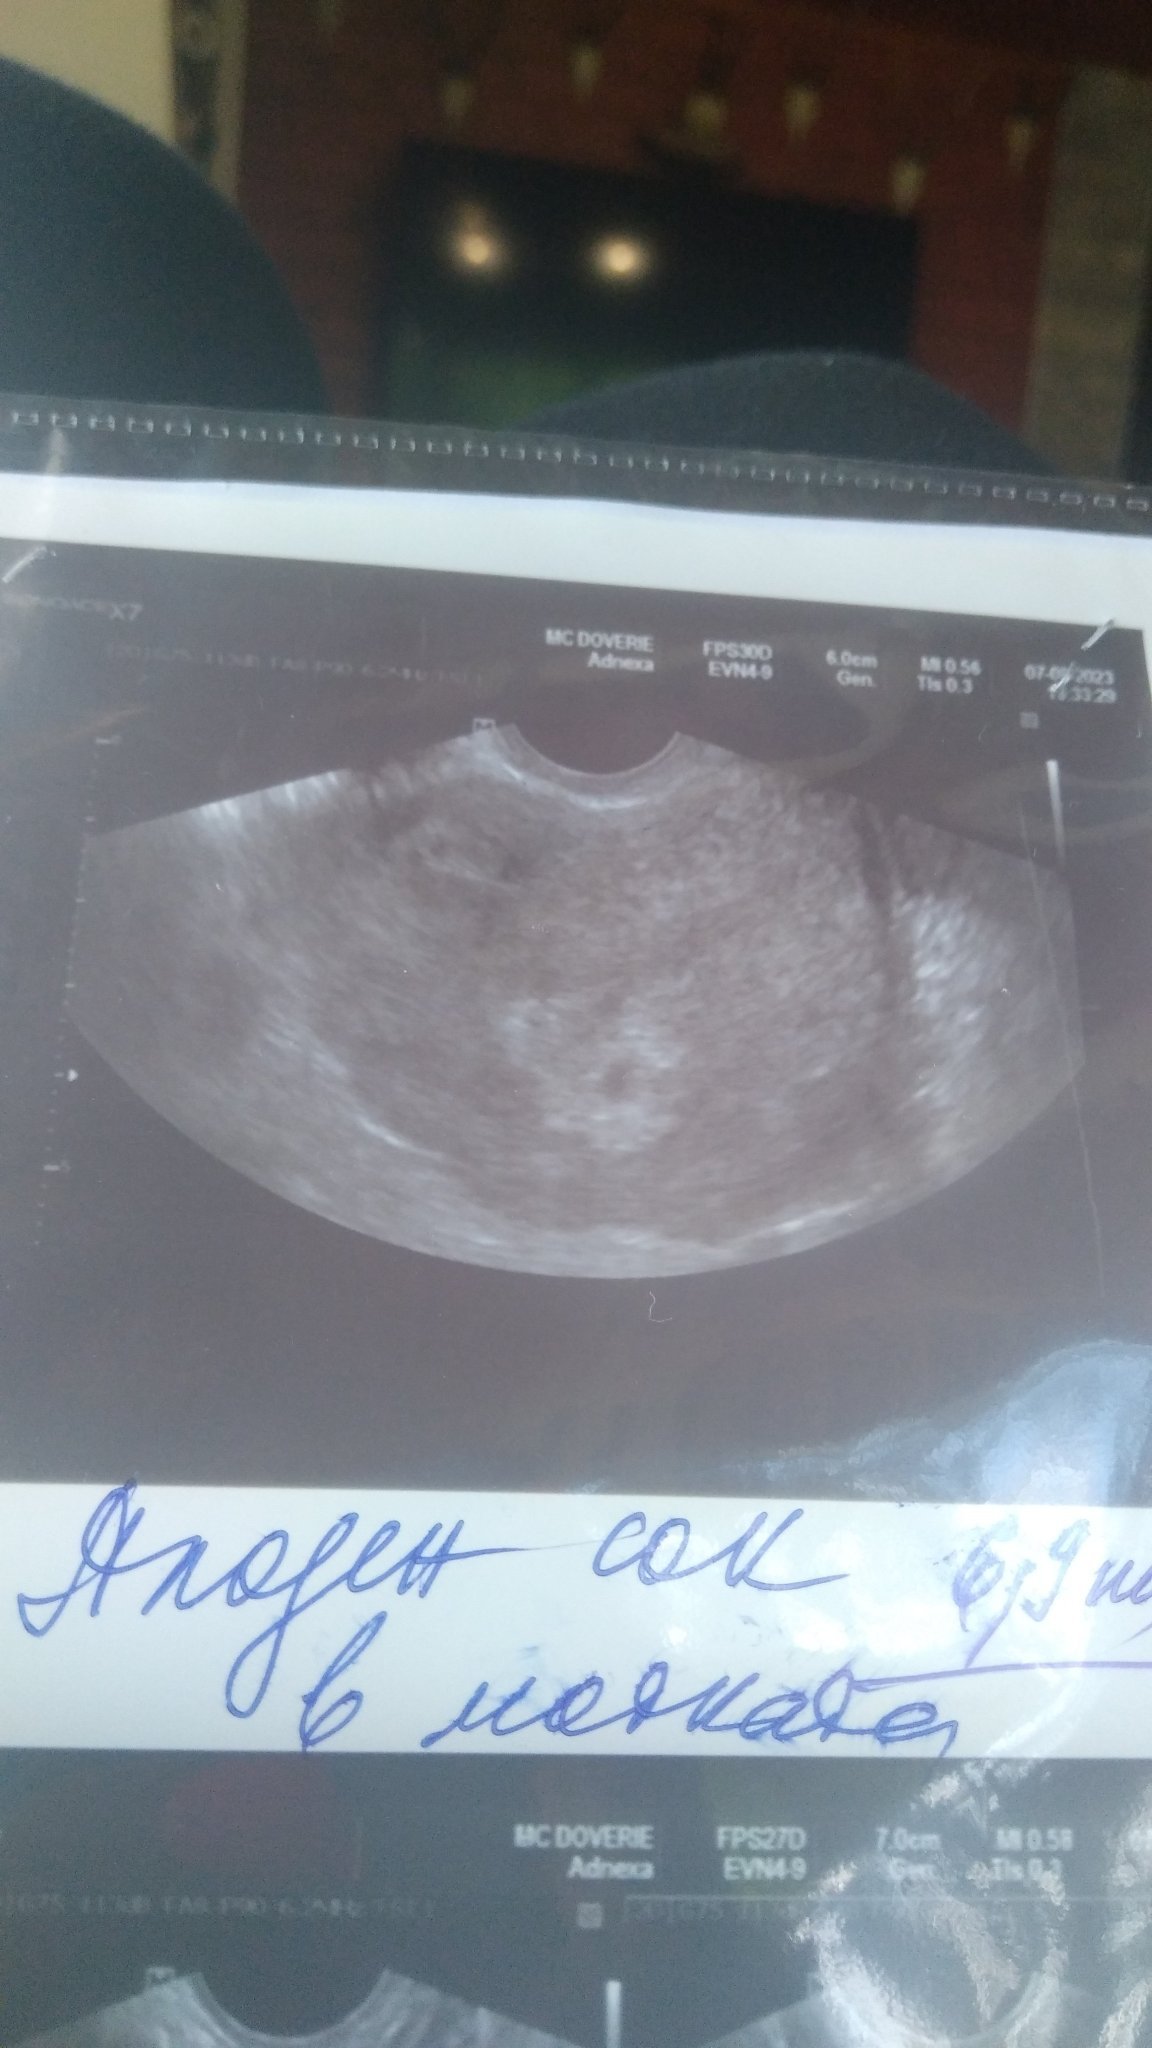

Здравейте не съм писала до сега днес бях на лекар каза че има плоден сак вие какво мислите

Прав е докторът,има плоден сак.Черната точка е сакът.